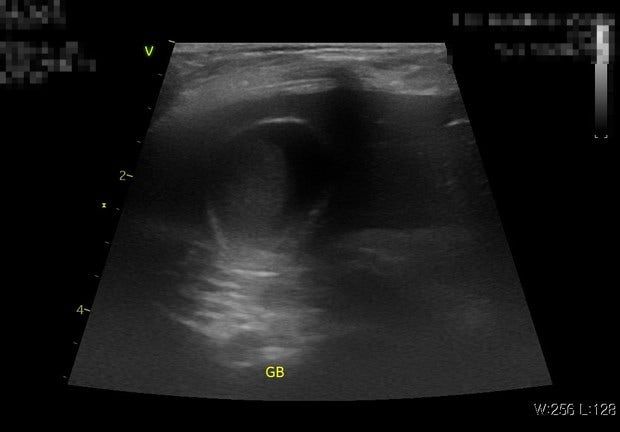

- 반려동물 건강반려동물Q. 강아지 담낭 한번 봐주시면 감사하겠습니다11살 푸들이고 슬러지는 6개월전에도 있었고 이 초음파 사진들은 찍은지 5일정도 안된것입니다두 병원 모두 슬러지라 했고 우루사를 처방안해주는데 정원하면 그건 보호자 선택사항이라는데 어떻게 보시나요? 제가 해줄수있는게 대체 뭐가 있을까요? 병원에선 유산균 파이보만 먹이라고하고 어떤 처방약도 안줬는데 파이보와 유산균을 줘봐도 (국내유산균은 원래 주고 있었습니다 파이보를 여기에 추가함 유산균 문제라고 생각하실수도있는데 미국 수의대학에서도 쓰고 있고 논문에서도 쓰고 있는 유산균입니다 국내 유산균이나 미국 유산균이나 결과는 같았습니다 나아지지가 않음) 변을 부분적으로 겉에 표면만 회색변을 눈다던지 표면적으로 겉에만 흰노란색 같은 변을 자주 놓고 소화불량도(트름이라던지, 바닥을 이유없이 계속 햙는다던지, 혀를 낼름거린다던지 복명음 등) 변비도 있고 장내미생물 불균형에 간균이 현미경 변검사에서 많았고 cpl 은 정상입니다